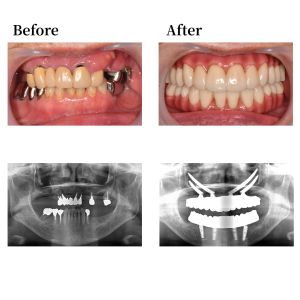

Case 55

背景

上顎骨の形状を整え、12、22の位置にザイゴマインプラントを52度傾斜埋入。15、25の位置にザイゴマインプラント60度傾斜埋入。下顎も形状を整え、45, 42, 32, 35の位置にそれぞれオールオン4インプラントを埋入。 42, 32の位置に、0度垂直埋入、45, 35の位置に17度傾斜埋入。その後、マルチユニットアバットメントで角度補正を行い、プロビジョナルレストレーション(審美的な仮歯)を装着した。

上下顎はUTジルコニアで構成された、フルジルコニアブリッジでファイナルレストレーションとした。焼成されたジルコニアはステインテクニックで着色した。シェードカラーはA2。